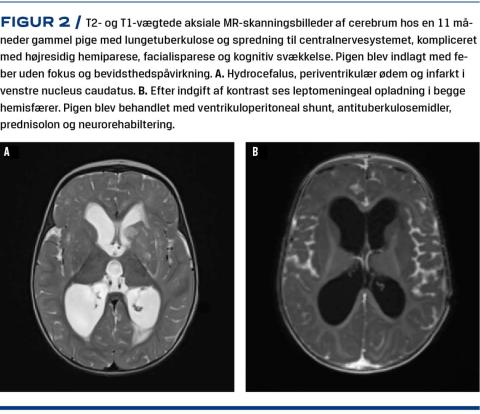

Klassiske symptomer på tb er hoste i mere end 2-3 uger, feber, vægttab, træthed og nattesved. På trods af omfattende sygdom kan børn have uspecifikke symptomer og objektive tegn og kan debutere med dårlig trivsel, nedsat aktivitetsniveau og symptomer, der kan mistolkes som almindelige luftvejsinfektioner. Lunge-tb er den hyppigste sygdomsmanifestation [6, 7]. Ofte er der sparsomme fund på røntgenbilleder af thorax, men i forskelligt omfang kan der ses kaviteter, persisterende lungeinfiltrater, atelektase, intratorakal lymfadenopati, bronkial obstruktion og/eller pleuraansamlinger som hos voksne [10]. Ekstrapulmonal tb er hyppigere hos børn end hos voksne og ses hos ca. 25% af de afficerede, ofte i lymfeknuderne, men alle organer kan afficeres, og spektret af symptomer og kliniske fund er derfor meget bredt [7]. Tuberkuløs meningitis og miliær tb er forbundet med en høj mortalitet og risiko for sequelae, særligt hos immunsupprimerede og små børn (Figur 2) [11]. Som differentialdiagnose bør tb-meningitis overvejes hos alle børn med bevidsthedspåvirkning, særligt ved risikofaktorer såsom hiv-infektion, immunsuppression, forældre fra højendemiske lande m.m.

TAKSIGELSE: Christian Rahbek, Røntgen og Skanning, Neuroradiologisk Afdeling, Aarhus Universitetshospital, takkes for bidrag i form af MR-skanningsbilleder af cerebrum. Peter Henrik Andersen, Infektionsepidemiologi og Forebyggelse, Statens Serum Institut, takkes for levering af data til Figur 1.